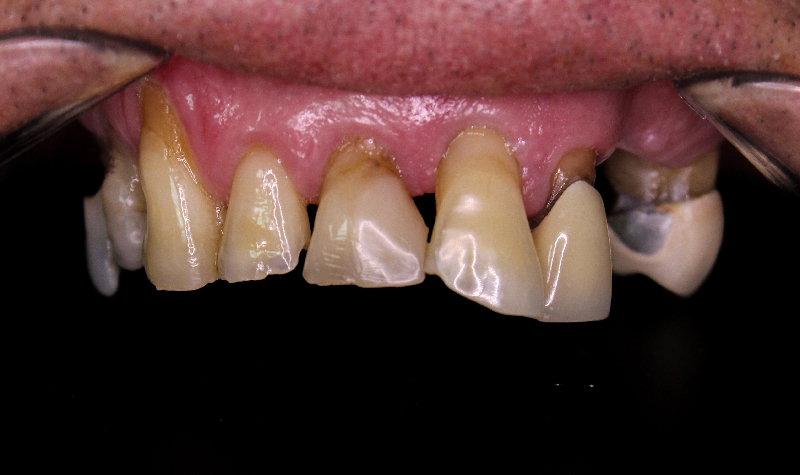

Rehabilitación oral total de alta complejidad con cerámicas sobre dientes e implantes.